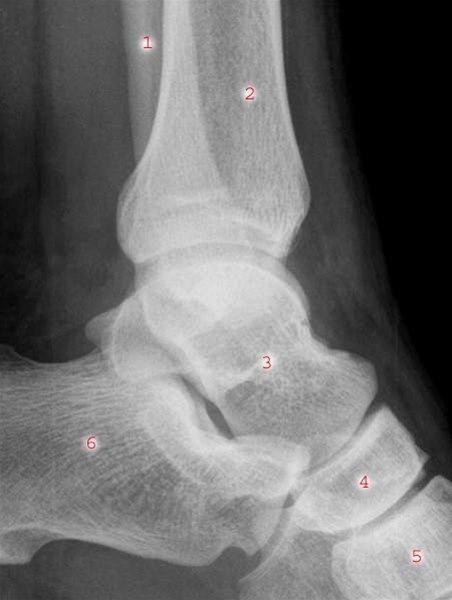

Ankelleddene er meget utsatte for skader fordi de er ganske bevegelige og belastes med hele kroppens tyngde. Det skilles et øvre og et nedre ankelledd. Det øvre ankelleddet utgjøres av tre ben: de nedre delene av skinnebenet (tibia) og leggbeinet (fibula), og ankelbeinet (talus). Det nedre ankelleddet dannes av tre ben: hælbeinet (calcaneus), ankelbeinet (talus) og båtbenet (os naviculare). Det er det øvre ankelleddet som denne artikkelen handler om. Leddet stabiliseres av ankelgaffelens form og leddbånd på innsiden (medialt), utsiden (lateralt) og mellom de to leggbeina (syndesmosen - et bånd som binder sammen de to beina). Se illustrasjon av ankelleddet nedenfor sett bakfra og fra siden, og røntgenbilde tatt skrått bakfra og fra siden.